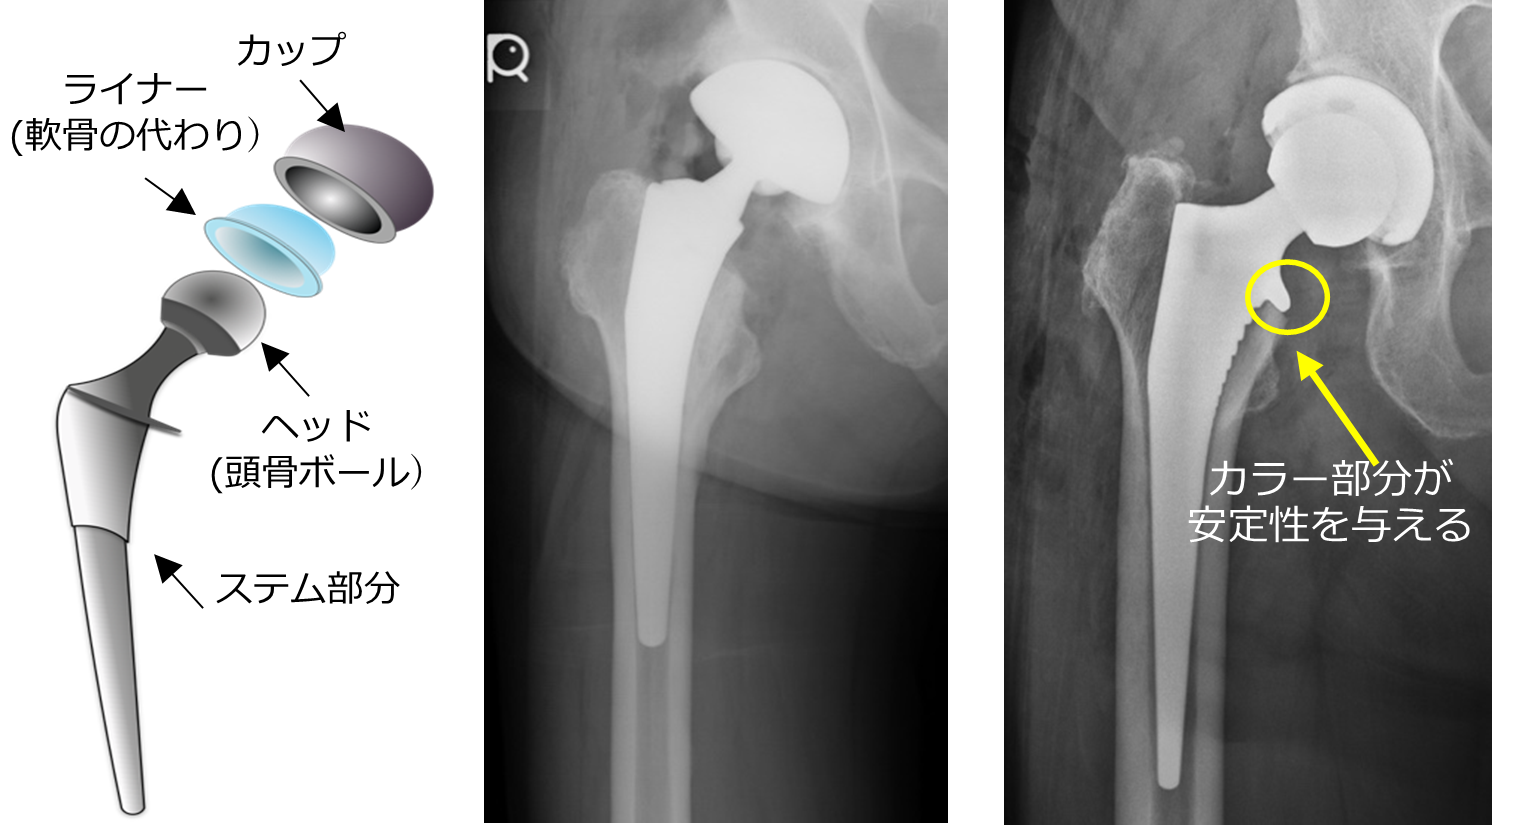

人工股関節全置換術後の骨折予防に新展開?-カラー(襟)付きHAステムの有効性に期待-

2025年10月28日

- 研究・産学連携